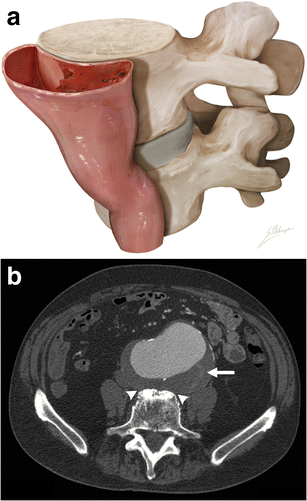

Draped aorta sign. a Illustration depicts loss of normal aneurysm wall convexity. The posterior wall of the aorta moulds to the anterior surface of the vertebral body. b Axial enhanced CT of an 85-year-old man with abdominal pain. The posterior aortic wall follows the contour of the anterior portion of the vertebra, with loss of fat planes between the aneurysm and vertebra (white arrowheads). Discrete thrombus fissuration (white arrow) is also seen. These are both signs of impending AAA rupture